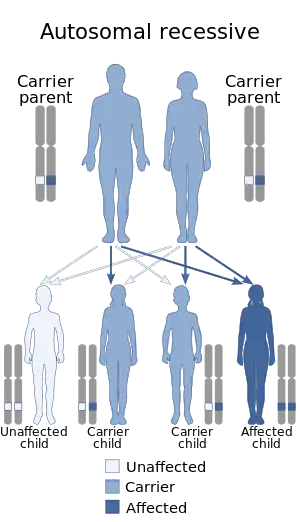

| Mitochondrial DNA depletion syndrome is inherited in an autosomal recessive manner | |

Mitochondrial DNA depletion syndrome (MDS or MDDS), or Alper's disease, is any of a group of autosomal recessive disorders that cause a significant drop in mitochondrial DNA in affected tissues. Symptoms can be any combination of myopathic, hepatopathic, or encephalomyopathic.[1] These syndromes affect tissue in the muscle, liver, or both the muscle and brain, respectively. The condition is typically fatal in infancy and early childhood, though some have survived to their teenage years with the myopathic variant and some have survived into adulthood with the SUCLA2 encephalomyopathic variant.[2][3] There is currently no curative treatment for any form of MDDS, though some preliminary treatments have shown a reduction in symptoms.[4]